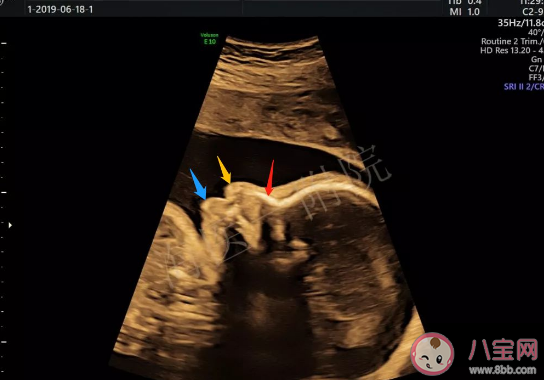

孕期時要定期產檢,既是檢查寶寶發育情況,也是檢查孕媽的身體情況,大人和小孩都是要特別注意的哦。孕檢說胎兒腿短以后長不高嗎 胎寶寶腿短孕媽媽吃啥。八寶網帶來相關介紹。